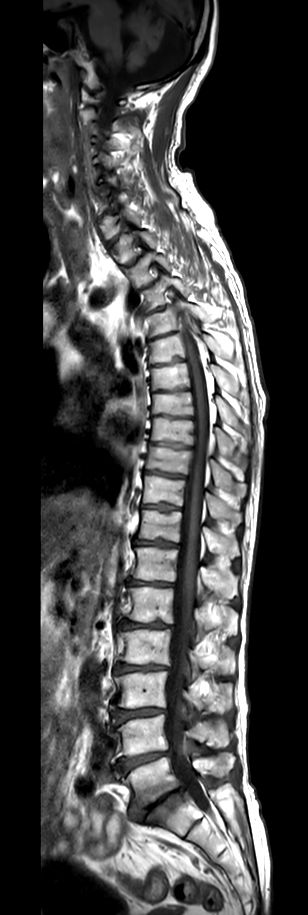

Sagittal T2w TSE (2 stations)Compressed SENSE